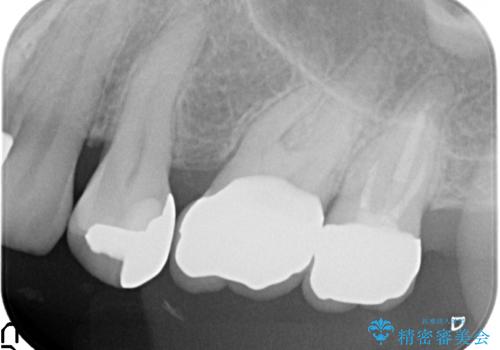

治療後はしみなくなり、違和感のない自然な咬み心地にご満足頂けました。

「割れる心配のないゴールドにしたいけれど、目立ってしまうかしら...」と心配されており、不要に歯質を削合しないよう注意を払い最小限の大きさのインレーを装着したところ、「あまり目立たなくて良かった!」とおっしゃって下さいました。

審美面でセラミックに劣りますが、奥歯の治療には最適な材料です。